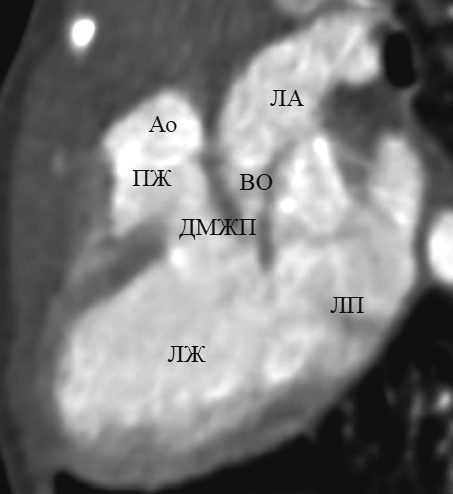

При транспозиции в этой реформации, в отличие от нормы, выходные тракты и магистральные артерии расположены параллельно. При этом визуализируются два параллельно расположенных сосуда: аорта — спереди от легочной артерии, которая является продолжением правого желудочка; легочная артерия — кзади от аорты, которая является продолжением левого желудочка (рис. 7, а). Параллельный ход магистральных артерий четко визуализируется и в реформации приточных отделов желудочков.

Рис. 7. В реформации по длинной оси левого желудочка при транспозиции магистральных сосудов: выходные тракты и магистральные артерии расположены параллельно (а); определяются митральное полулунное фиброзное продолжение (b, стрелка) и дефект межжелудочковой перегородки (c, стрелка). Ао — аорта; ЛА — легочная артерия; ЛЖ — левый желудочек; ПЖ — правый желудочек

Fig. 7. Long-axis of left ventricle reformation in great arteries transposition: outflow tracts and great arteries are parallel (а); semi-lunar fibrous prolongation (b, arrow) and interventricular sept defect (c, arrow) are determined. Ао – aorta; ЛА – pulmonary artery; ЛЖ – left ventricle; ПЖ – right ventricle

Достоверно визуализировать митрально-полулунное фиброзное продолжение, представляющее собой фиброзный контакт легочного клапана с митральным клапаном, при транспозиции удалось в 10 случаях (рис. 7, b). Дефект межжелудочковой перегородки визуализировался во всех случаях (рис. 7, c). В реформации по длинной оси левого желудочка удалось определить стеноз выходного тракта левого желудочка (рис. 8).

Рис. 8. В реформации по длинной оси левого желудочка при транспозиции магистральных сосудов определяется сужение выходного отдела левого желудочка. Ао — аорта; ЛА — легочная артерия; ВО — выходной отдел; ДМЖП — дефект межжелудочковой перегородки; ЛЖ — левый желудочек; ЛП — левое предсердие; ПЖ — правый желудочек

Fig. 8. Long-axis of left ventricle reformation in great arteries transposition: narrowing of the output portion of the left ventricle is determined. Ао – aorta; ЛА – pulmonary artery; ВО – the output portion; ЛЖ – left ventricle; ЛП – left atrium; ПЖ – right ventricle

При корригированной транспозиции в этой реформации выходные тракты и магистральные артерии расположены параллельно. При этом визуализируются параллельно расположенные желудочки с отходящими от них магистральными сосудами: аорта — спереди от легочной артерии, которая служит продолжением морфологически левого желудочка; легочная артерия — кзади от аорты, которая служит продолжением морфологически правого желудочка.